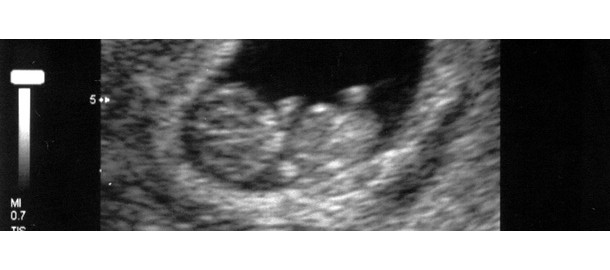

De ChristenUnie wil dat staatssecretaris Bussemaker onderzoek doet naar het verband tussen de 20-weken echo en het aantal late abortussen. Voorgaande jaren werd er nauwelijks tot geen melding gemaakt van levensbeëindiging bij pasgeborenen. De partij vraagt zich af dit betekent dat ongeboren kinderen met een beperking vrijwel altijd na de 20-weken echo en voor de toegestane termijn van 24 weken, worden geaborteerd.